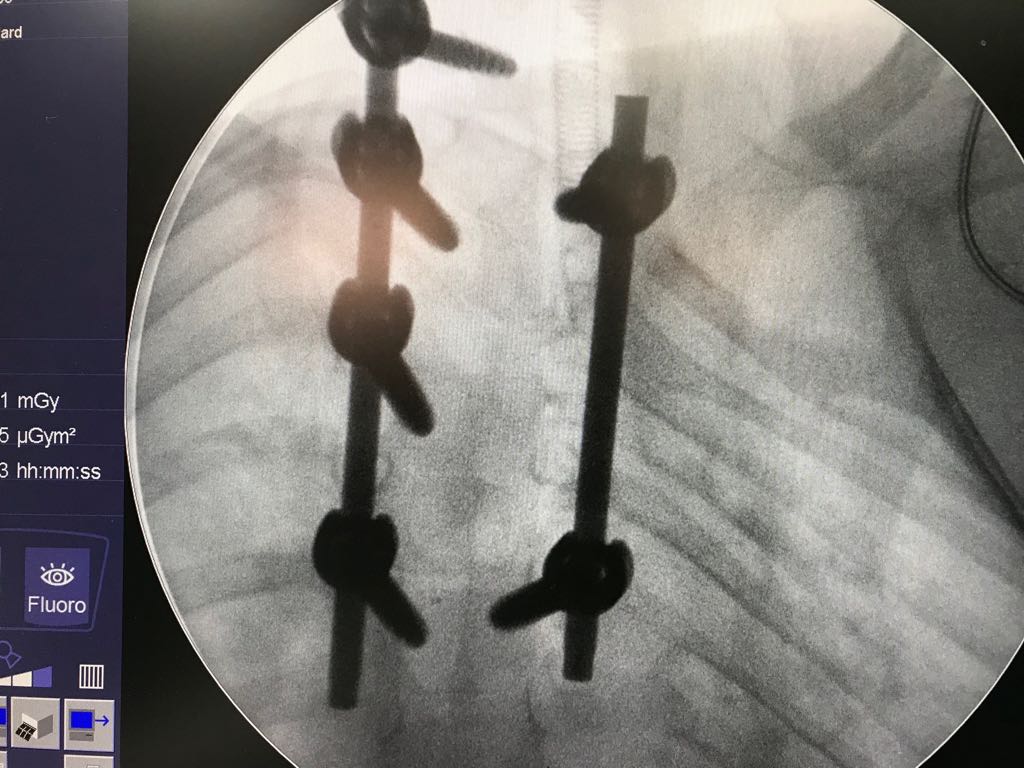

Hemivebra eksizyonu ve bar osteotomisi yapıldı.

Ameliyat Görüntüleri